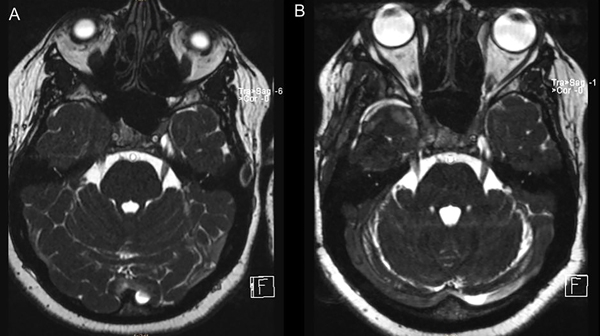

La anatomía patológica informó lesión compatible con pseudotumor inflamatorio. Realizó un mes de tratamiento con corticoides. Se realizó RMN de control a los 2 meses en la que se evidenció importante reducción del volumen de la lesión (Figura 2 y 3).

Figura 3. RMN secuencia CISS preoperatoria (A) y control a los 2 meses (B).